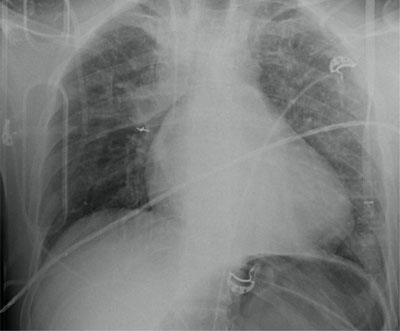

Figure 1

Multiple left sided rib fractures without pneumothorax and blurry consolidations in both lungs, probably lung contusions.